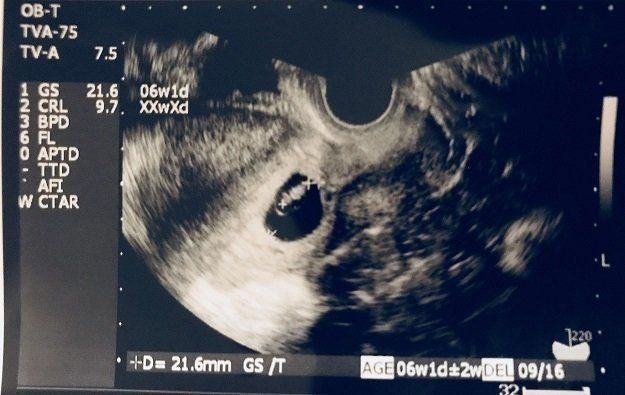

たかこさんの妊娠6週目のエコー写真 ようやく心拍を確認するも、まだ気が抜けない時期

めまいに加えて、つわりが出始めました。不正出血から1週間後の検査で、胎嚢の中に胎芽と心拍を確認。左上にちょこんと、くっついています。前回、心拍確認後の流産だったため、「もう少し様子を見ようか」と、この時点ではまだ母子手帳をもらってくるようには言われませんでした。なお、エコー写真に記載される週数は、胎嚢、胎芽の大きさで計るために、1週間たってもまだ5週と表示されています。